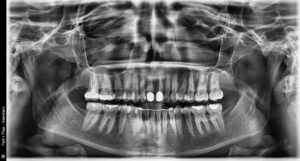

Please use the panoramic film below to answer the question below.